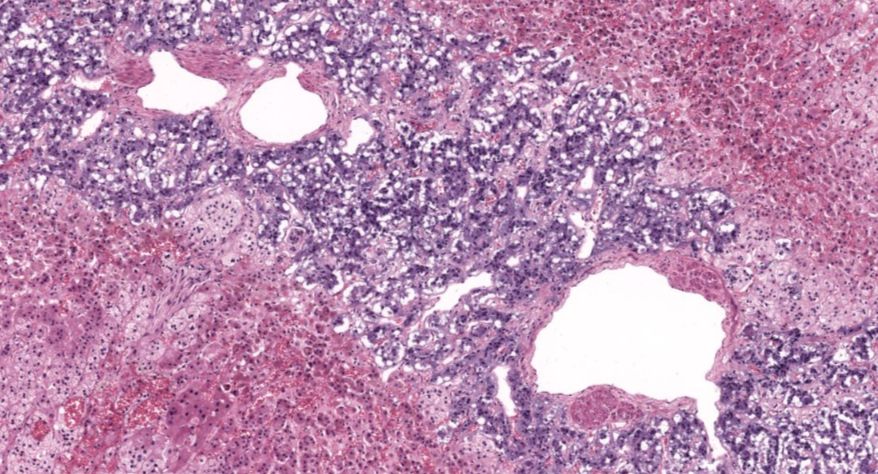

肾上腺

1.全景图